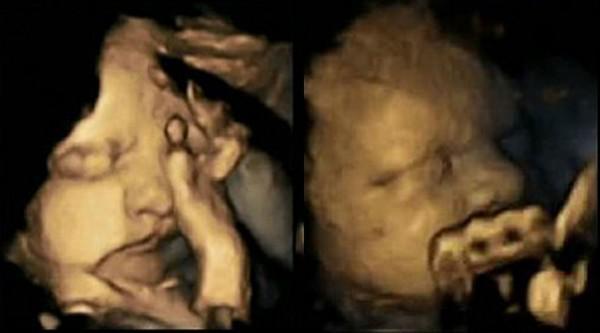

Les images obtenues pendant l'étude (à gauche le foetus d'une fumeuse, à droite le foetus d'une non fumeuse) :

La médecin a pratiqué une échographie 4D à la 24ème, 28ème, 32ème et 36ème semaine pour chaque sujet. Résultat ? Les foetus de femmes enceintes qui fument, bougent plus la bouche et se touchent plus le visage que les foetus dont la mère ne fume pas. Selon le Dr Nadja Reissland, plus un foetus se développe, moins il bouge, car il gagne en contrôle sur ses mouvements. Pour la spécialiste, cela signifierait donc que fumer pendant une grossesse ralentit le développement du système nerveux du foetus. Avant de confirmer officiellement cette hypothèse le médecin prévoit de refaire l'étude avec plus de cas.